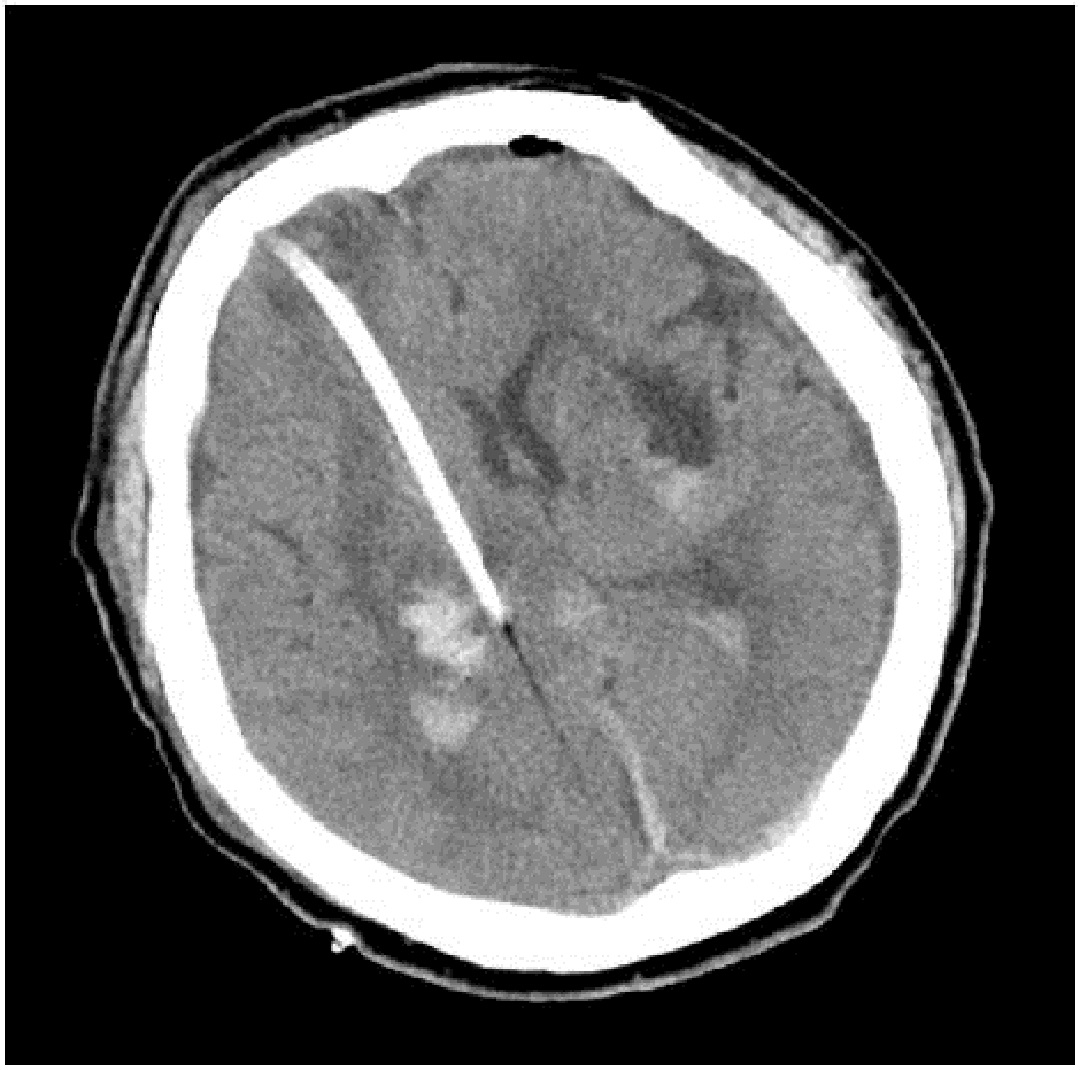

術(shù)前將導(dǎo)板放于術(shù)區(qū),標(biāo)記穿刺體表位置。術(shù)區(qū)消毒,橫切口長3cm,鉆骨孔切開硬腦膜,以鼻根及額部標(biāo)記,將導(dǎo)板用無菌薄膜包好后置于病人面部,使模型與病人面部緊密吻合,12號顱腦引流穿刺器放入穿刺通道內(nèi),緊貼內(nèi)壁,緩慢推進(jìn)至設(shè)定深度(9.5cm)拔出針芯,可見陳舊性血性液流出,固定引流管,一次性成功穿刺血腫,手術(shù)操作時間僅用15 min。(見下圖):

術(shù)后當(dāng)天CT

術(shù)后間斷注射尿激酶2萬單位,夾閉引流管3 h后開放,共注射四次,1天后復(fù)查頭顱CT,如下圖:

CT顯示血腫基本全部引出,患者意識恢復(fù)良好,拔去引流管,目前此患者已經(jīng)出院回家休養(yǎng)。